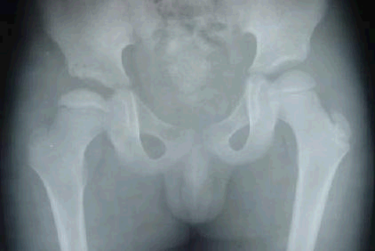

单选题 观察下面X线平片,你的诊断为

A. 左侧髋关节先天性脱位

B. 左侧股骨头骨骺缺血坏死

C. 右侧髋关节先天性脱位

D. 右侧股骨头骨骺缺血坏死